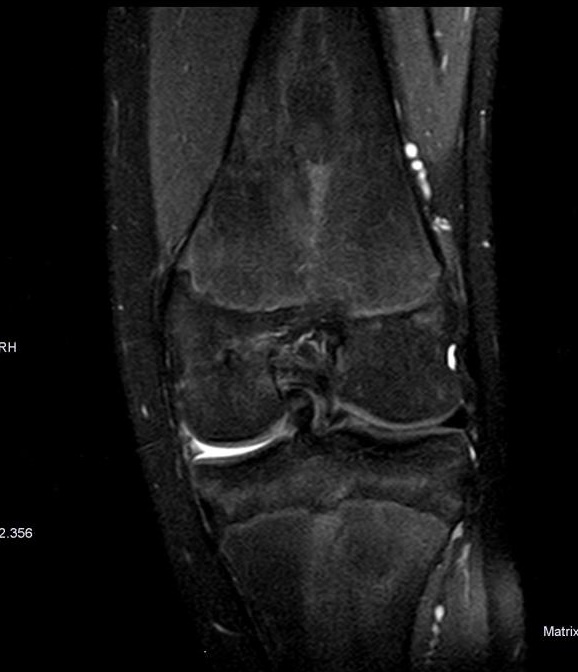

El paciente presenta signos meniscales positivos por lo que se haría una resonancia magnética ya que es la prueba que nos permite su visualización. Ante la sospecha clínica de lesión ligamentosa o meniscal, la prueba de elección es la resonancia magnética gracias a su elevada sensibilidad.